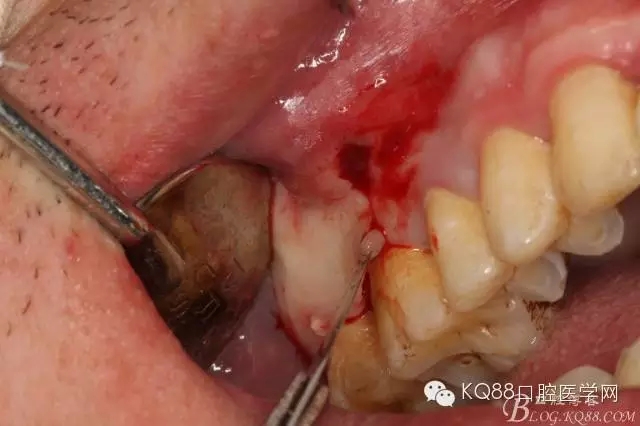

圖6.局部浸潤麻醉下。在16的近中做垂直切口+遠(yuǎn)中齦溝內(nèi)及上頜結(jié)節(jié)水平切口

圖7.翻全厚瓣。發(fā)現(xiàn)17牙根方的骨質(zhì)破損,破損處有大量膿性血性分泌物溢出。

圖8.繼續(xù)翻瓣至上頜結(jié)節(jié)處,發(fā)現(xiàn)骨壁缺損有花生米大小,腔隙內(nèi)有大量肉芽組織。

圖9.清理缺損骨腔內(nèi)的膿性分泌物及炎性肉芽組織,目的是找到18在哪里,隱約可以看到18白色的小樣子喲。